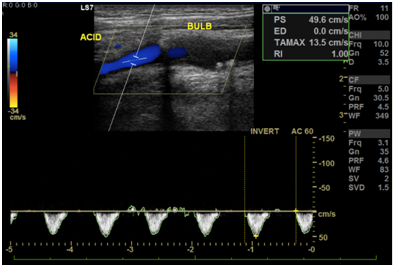

Cranioencephalic computerized tomography excluded acute ischemic lesions.CDS revealed severe stenosis of the innominate artery (PS 38 cm/s) (Figure 1), occlusion of right vertebral artery, total flow inversion of the right internal carotid artery (ICA) (Figure 2), partial endosystolic flow inversion of right CCA (Figure 3) and low amplitude anterograde flow of right external carotid artery, no significant lesions were found on the left carotid axis. Computerized tomography angiography (CTA) excluded significant carotid lesions and revealed pre-occlusive stenosis of the innominate artery by a calcic lesion (Figure 4).Surgical approach consisted of ultrasound-guided puncture of right brachial artery and surgical exposure of right CCA. Brain protection was achieved by direct clamping of the common carotid artery and subsequently carotid and axillary retrograde endovascular access was obtained. Placement of 6F introducer on brachial artery and 8F on right CCA (Figure 5). After pre-dilatation with a 4x40mm balloon (Admiral Xtreme™, Medtronic), a kissing stent technique was performed with a 6x59mm covered stent (AdvantaV12™, Getinge) on the right CCA and 7x57mm balloon-expandable stent (Visi-Pro™, Medtronic) on the right subclavian artery. At the end of the procedure direct expulsion of eventual embolic material was performed prior to declamping and a good permeability of the revascularized arteries was verified (Figure 6). Clamping time was under 1minute. The postoperative period was uneventful and patient was discharged 3days later.

Figure 1 Stenosis of the innominate artery.